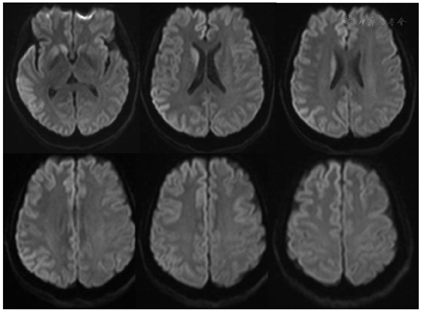

入院后完善血细胞分析、凝血功能、血糖、血脂、电解质、肝功能、肾功能、心肌酶、B型利钠肽、乙肝、梅毒、丙肝、HIV、铁蛋白、维生素B12、叶酸、甲状腺功能、抗核抗体、ANCA相关血管炎抗体等相关检测均未见异常。肿瘤标志物检测提示神经元特异性烯醇化酶测定38.36 ug/L(参考范围0~16.3 ug/L)。腰椎穿刺脑脊液压力53.2 mmH2O,脑脊液总细胞460×106/L,白细胞2×106/L。脑脊液蛋白、葡萄糖、氯化物、腺苷脱氨酶、乳酸均正常。脑脊液宏基因组二代测序(NGS)、自身免疫性脑炎相关抗体、脱髓鞘疾病相关抗体、副肿瘤神经综合征抗体、脑脊液寡克隆带及血清寡克隆带均阴性。头部MRI平扫及增强检查显示右额颞顶、左额皮层脑回样略高信号影,双侧尾状核头异常信号,右侧为著,未见明显强化改变(图1)。头颈及主动脉弓以上CTA检查未见大血管狭窄及异常。24 h动态脑电图提示各导联持续呈现广泛性间隔0.5~1 s中高幅周期性三相波,多以右额颞导联波幅较高,且各导联可见大量散在中高幅不规则慢波及短中程6Hz中幅慢波活动。脑脊液14-3-3蛋白检测结果阴性。患者PRNP基因检测显示无与遗传型朊病毒疾病相关的突变,PRNP基因129位氨基酸多态性为M/M型。脑脊液朊病毒检测(RT-QuIC技术)结果阳性。

患者存在快速进展的认知功能减退,锥体外系症状,无动性缄默,MRI显示双侧尾状核头、壳核及双侧皮层"花边样"高信号等特征性改变,脑脊液中可检出致病性朊蛋白,根据美国国家克-雅病研究和监测单位(NCJDRSU)2020年最新临床指南[1],本例诊断临床很可能的散发型克-雅病。